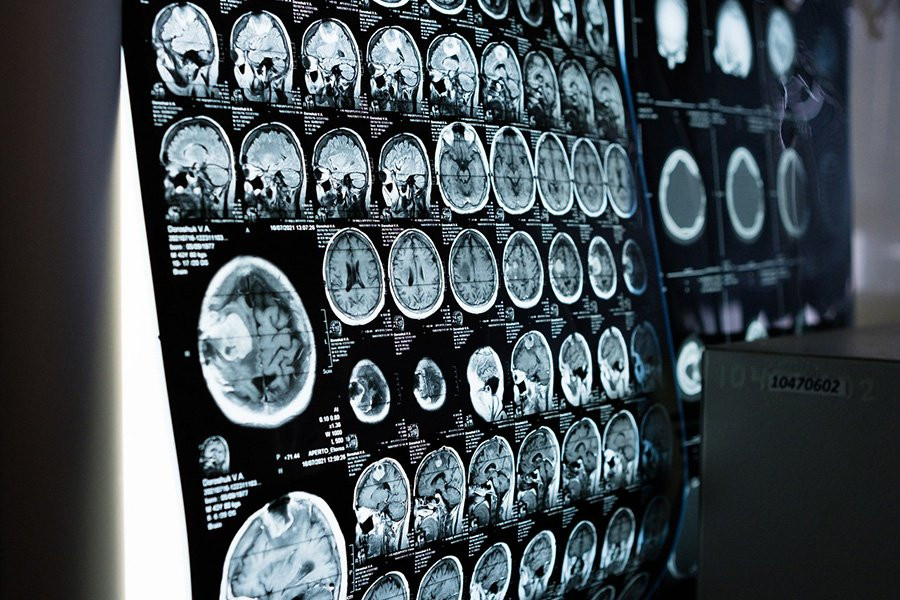

Чтобы решить этот вопрос по-другому, команда Менона использовала относительно новый метод, называемый фМРТ динамической функциональной связи. Это включает в себя запись активности мозга людей, пока они лежат, в функциональном МРТ-сканере и отслеживание изменений в том, как активность различных областей изменяется синхронно друг с другом.

Исследователи разработали ИИ для анализа таких данных сканирования мозга, которые они обучили на результатах примерно 1000 молодых людей из существующей в США базы данных под названием Human Connectome Project, сообщая ИИ, какие люди были мужчинами, а какие женщинами. В этом анализе мозг был разделен на 246 различных областей.

После этого процесса обучения ИИ с точностью около 90 процентов различал второй набор данных сканирования мозга тех же 1000 мужчин и женщин.

Что еще более важно, ИИ одинаково эффективно различал снимки мозга мужчин и женщин из двух разных наборов данных сканирования мозга, которых он раньше не видел. Оба они состояли из примерно 200 человек примерно одного возраста от 20 до 35 лет из США и Германии.